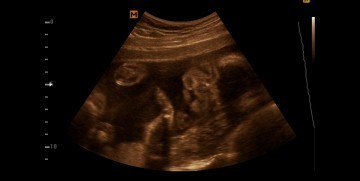

Cleft lip

Hi mommies, check up ko yesterday and nakita ni Dra. na hindi daw nagdevelop yung sa labi ng baby ko. Meron syang left lip. ? but still pray lang ako na sana magdevelop pa sya. And im so happy na din kasi yun lang ang defect nya.

hi momsh! sorry naopen ko ulit ang topic mo alam ko pong matagal na ito, same po kasi tayo nadetect sa CAS ko na may upper lip defect si baby. 25weeks preggy po ako now, kamusta na po ang baby nyo? salamat po God bless po momsh!